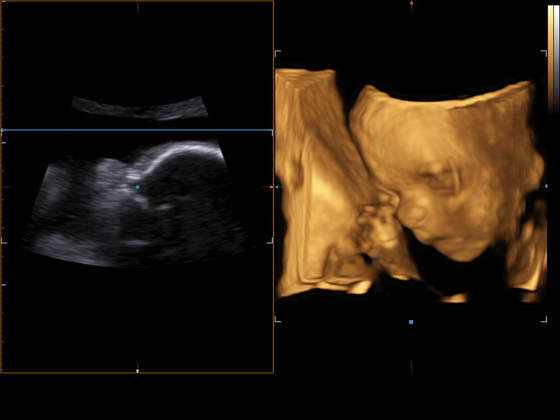

Dziewczyny, przedstawiam Wam Zosinkę

Dziś byliśmy na wizycie. Dziewuszka zdrowa, ruchliwa, w trakcie badania dostała czkawki

Następna wizyta 2 października, ale chyba bez USG.

No i ze mnie lekarz i położna zadowoleni, bo w końcu ruszyły mi kilogramy do przodu.

Niestety coś tam w badaniach odbiega od normy, ale to jak na razie do obserwowania.